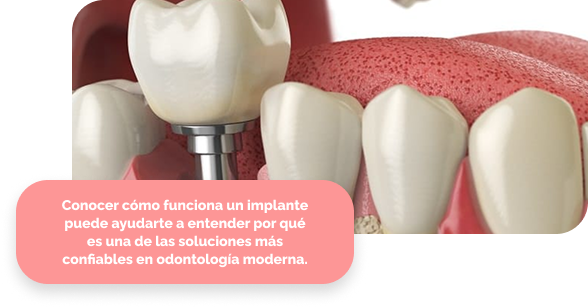

Un implante dental es una estructura de titanio que se coloca en el hueso maxilar para reemplazar la raíz de un diente perdido. Sobre él se fija una corona que imita la forma y función de un diente natural, integrándose de manera segura y estable.